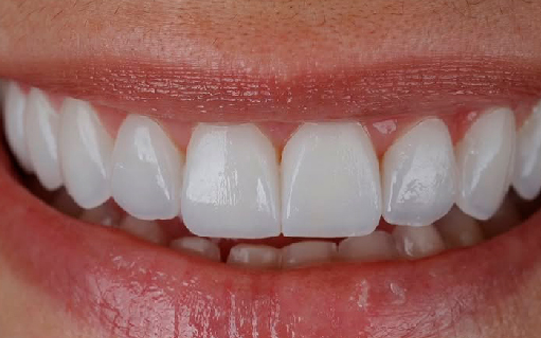

Protocolo em Resina Acrílica: boa estética, acessível, indicado para reabilitações com ótimo custo-benefício.

Esse é o momento perfeito para você trazer o seu sorriso de volta!